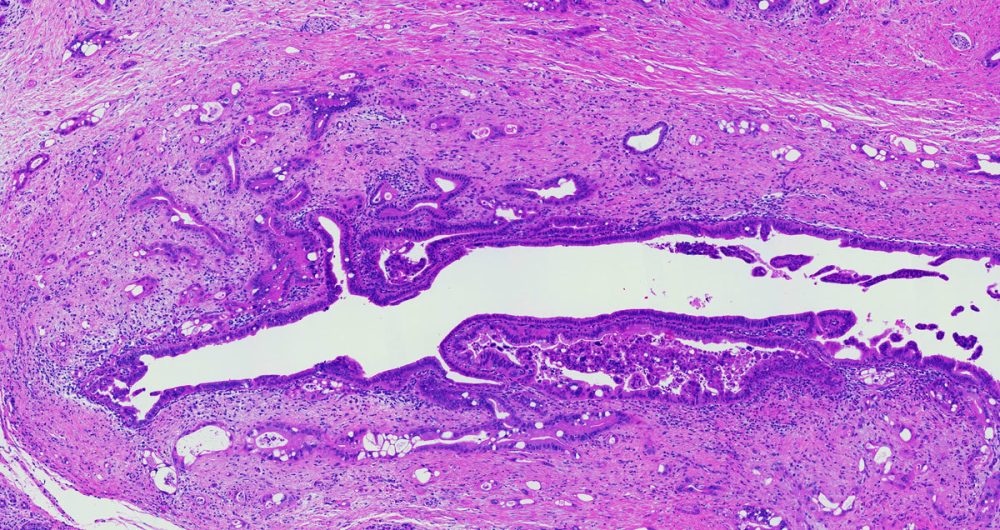

A small anatomic structure. This is essentially a tube that carries various bodily fluids. The pancreatic duct runs the full length of the pancreas and drains into the duodenum.

A term used to indicate that cancerous cells are present in the duct but have not yet invaded deeper tissues.

Microscopically, adenocarcinomas form glands. These tumors can grow large enough to invade nerves which can cause back pain. They also frequently spread (metastasize) to the liver or lymph nodes. If this happens the tumor may be considered unresectable.